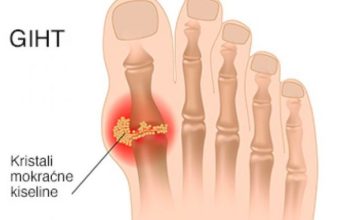

Često zijevanje, izbijanje gasova i hladna stopala: to su simptomi ove bolesti!

Jedna studija pokazuje da...